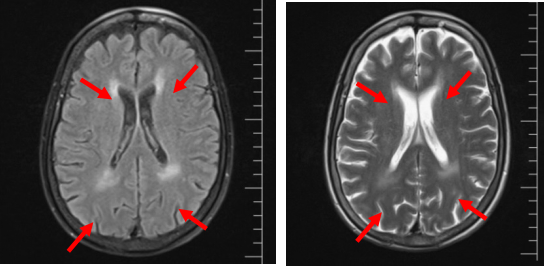

神经科会诊意外发现:神经内科会诊时详细追问病史,患者诉近年出现进行性听力下降、手足麻木,查体发现腱反射减弱。神经肌电图提示:多发慢性周围神经病,运动与感觉神经均有受累,以下肢为主;脱髓鞘伴轴索损害。头颅MRI示脑白质病变。

图3  头部MRI提示脑白质病变